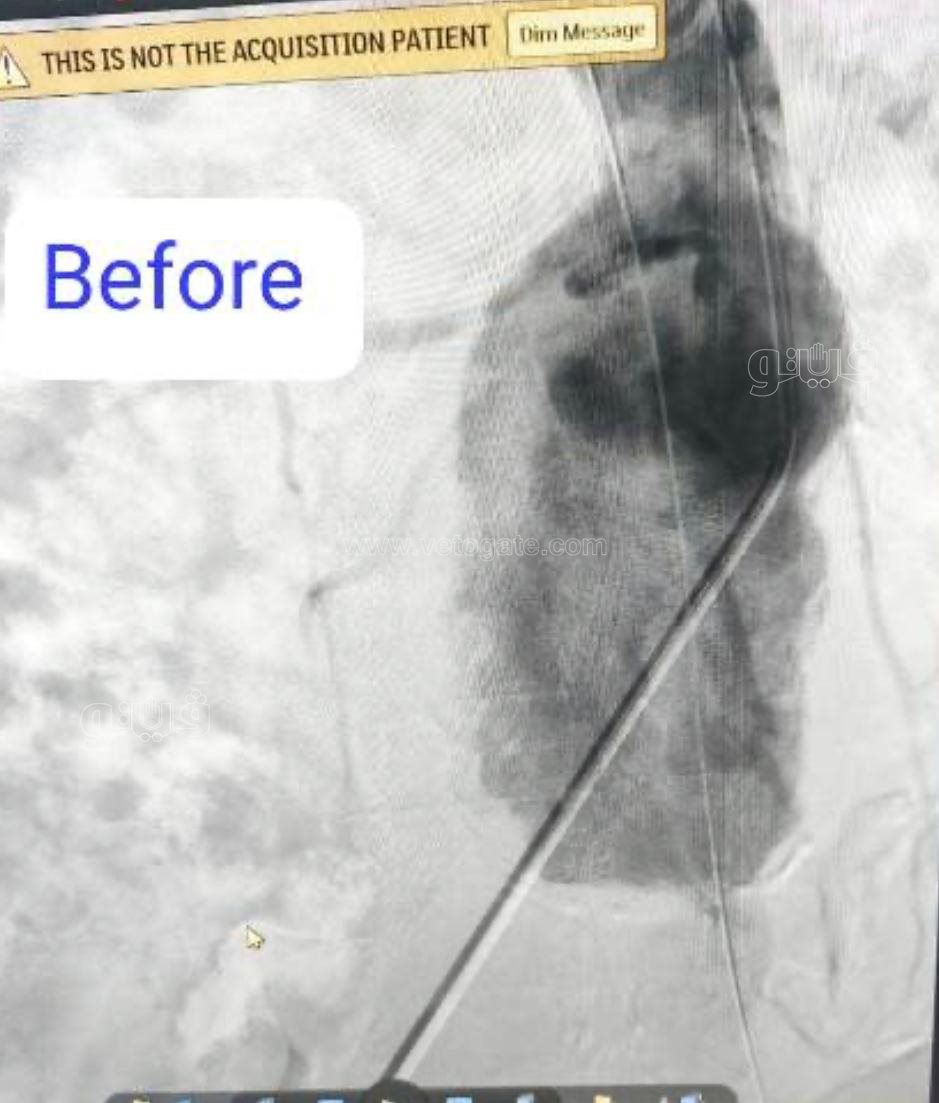

نجح فريق بقسم جراحة الأوعية الدموية بـ مستشفى بدر التابعة لكلية الطب بجامعة حلوان في إجراء تركيب قسطرة دقيقة جدًا لمريض يعاني من تمدد كبير في الشريان الأورطي والشريان الحرقفي الأيمن، حيث تم تثبيت دعامات مغطاة على هذين الشريانين لمنع انفجارهما، مما ساهم في إنقاذ حياته.

وأفاد الدكتور محمد فاضل، مدير مستشفى بدر أن الفريق الطبى الذى قام بإجراء القسطرة التشخيصية ضم كلًا من: " أحمد المهدى رئيس قسم جراحة الأوعية الدموية، شريف عمر كرداوى أستاذ جراحة الأوعية الدموية، أحمد عبد العليم مدرس جراحة الأوعية الدموية، حسام إبراهيم مدرس مساعد جراحة الأوعية الدموية، عمرو حسان مدرس مساعد جراحة الأوعية الدموية، أيمن مرسى، محمد مجدى، محمود أمير، مصطفى علاء، ومحمود العدل".